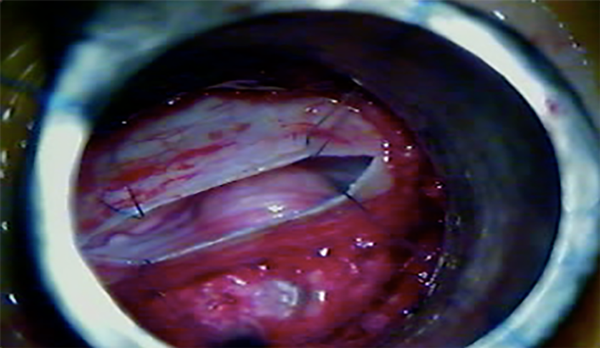

Cuando ya se encuentran en tracción los 4 puntos de reparo dural, los extremos de la incisión se aproximan entre sí, y eso permite incidir con bisturí dichos extremos para realizar una nueva tracción de los puntos de reparo, y así, una mayor exposición lateral (Fig. 7, 8 y 9).

Fig. 7: Ojal dural mediante retracción dural transtubular

Fig. 8: Disección tumoral separando la duramadre por apertura insuficiente.

Fig. 9: Exposición del contenido intradural mediante retracción dural percutánea.